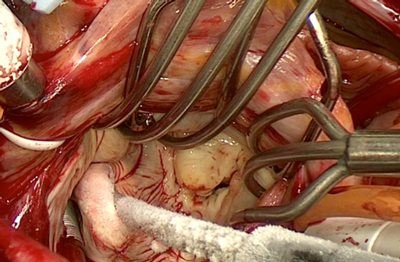

当院では、1992年から心房細動を手術で治療する「メイズ手術」を積極的に行っております。同手術は、不整脈の原因となる電気の流れを冷凍凝固により断ち切り(図1:水色線)、正しい電気の流れのみを残す手術になります。これまで合計1,100例を超える患者さんに行い、手術後1年で約92%の方が正しい脈に回復されています。